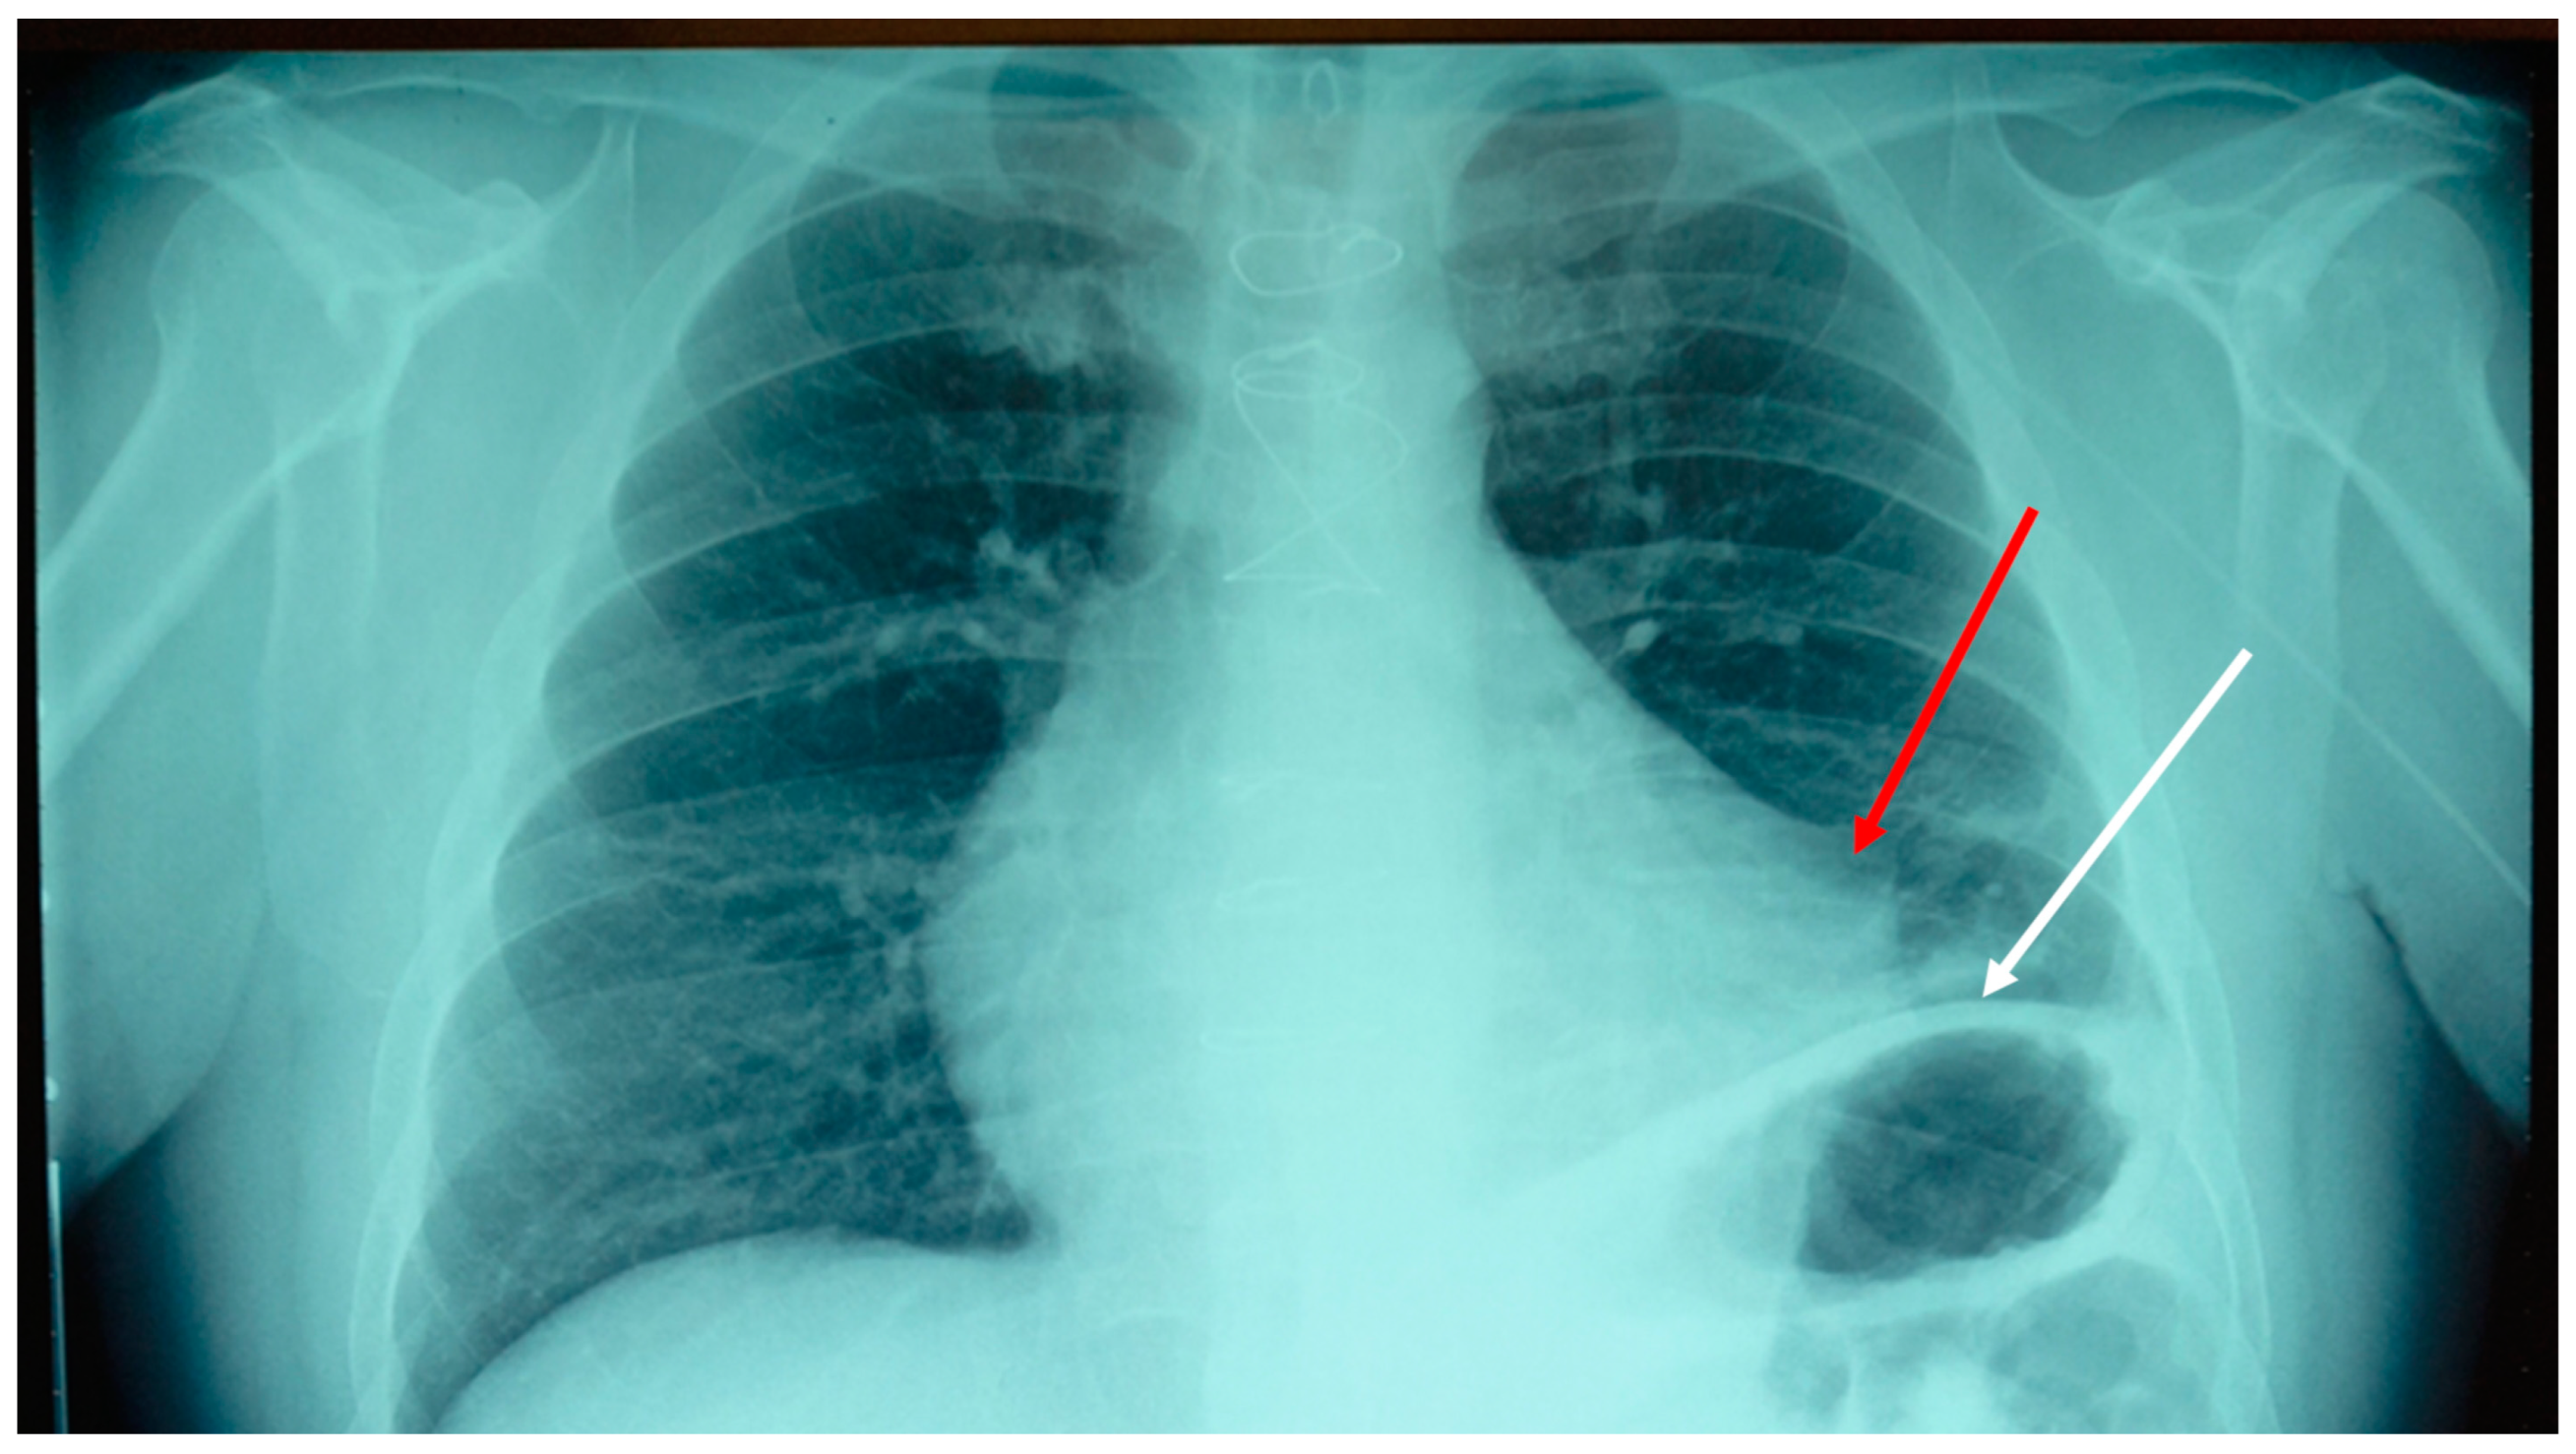

This test consists in pressing a tissue area (sternum), while with the other hand resting on the symptomatic area (the neck); the clinician tries to perceive a change in tone. Finally, the cervical spine area is pressed, and the response is felt from the sternal area [16]. The tissue that does not show any tone variation is, very similarly, the area of symptomatological derivation. In this case, the sternal and thoracentesis access area were the areas where the tissue tone did not change. Performing the Bordoni diaphragmatic test (BDT), the outcome gave a positive result of dysfunction of the diaphragm muscle [17]. It was decided to take a chest x-ray (Figure 1).

The result of the instrumental examination highlighted an adherence between the pericardium and the pleura in the left mediastinal area, and an elevation of the left hemidiaphragm. We decided to do an osteopathic treatment with a technique used in a previous trial, that is, an indirect approach [18]. The goal was to reduce pain and improve movement function. The clinician places one palm on the sternal area (involving the anterior pericardial area) and the other hand, open posteriorly, on the vertebral area of T10-T12; the latter thoracic area corresponds to the posterior attachment of the pericardium [19].

Figure 1. Anteroposterior chest x-ray shows an adhesion between the pericardial tissue and the pleural tissue of the left mediastinal area, probably due to a previous thoracentesis (red arrow). The left hemidiaphragm is visibly elevated due to a possible uninvestigated ipsilateral phrenic nerve lesion (white arrow).